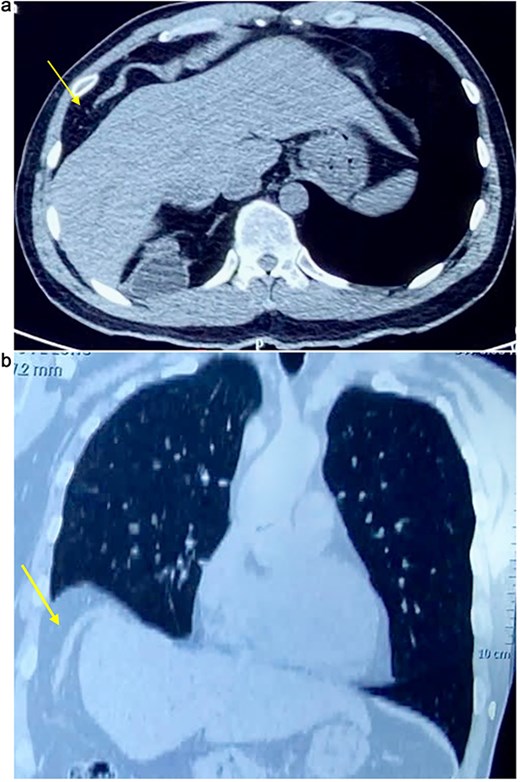

On physical examination, vital signs were stable, and there were no abnormalities. Blood tests and abdominal ultrasound were normal. Gastroscopy shows no lesions. Chest X-ray shows an elevated right hemidiaphragm (Fig. 1). Computed tomography (CT) scan revealed a discontinuity of the right diaphragmatic muscle near the chest wall, with an ~9 × 5 cm hernia defect. This defect established communication between the peritoneal fat and the right pleural space at the lung base (Fig. 2a and b).

(a) Axial CT scan showing an arrow pointing to a discontinuity of the right diaphragm muscle near the right chest wall. (b) Transverse CT scan showing an arrow pointing to a communication between the peritoneal fat of the abdominal cavity and the right pleural space at the lung base.